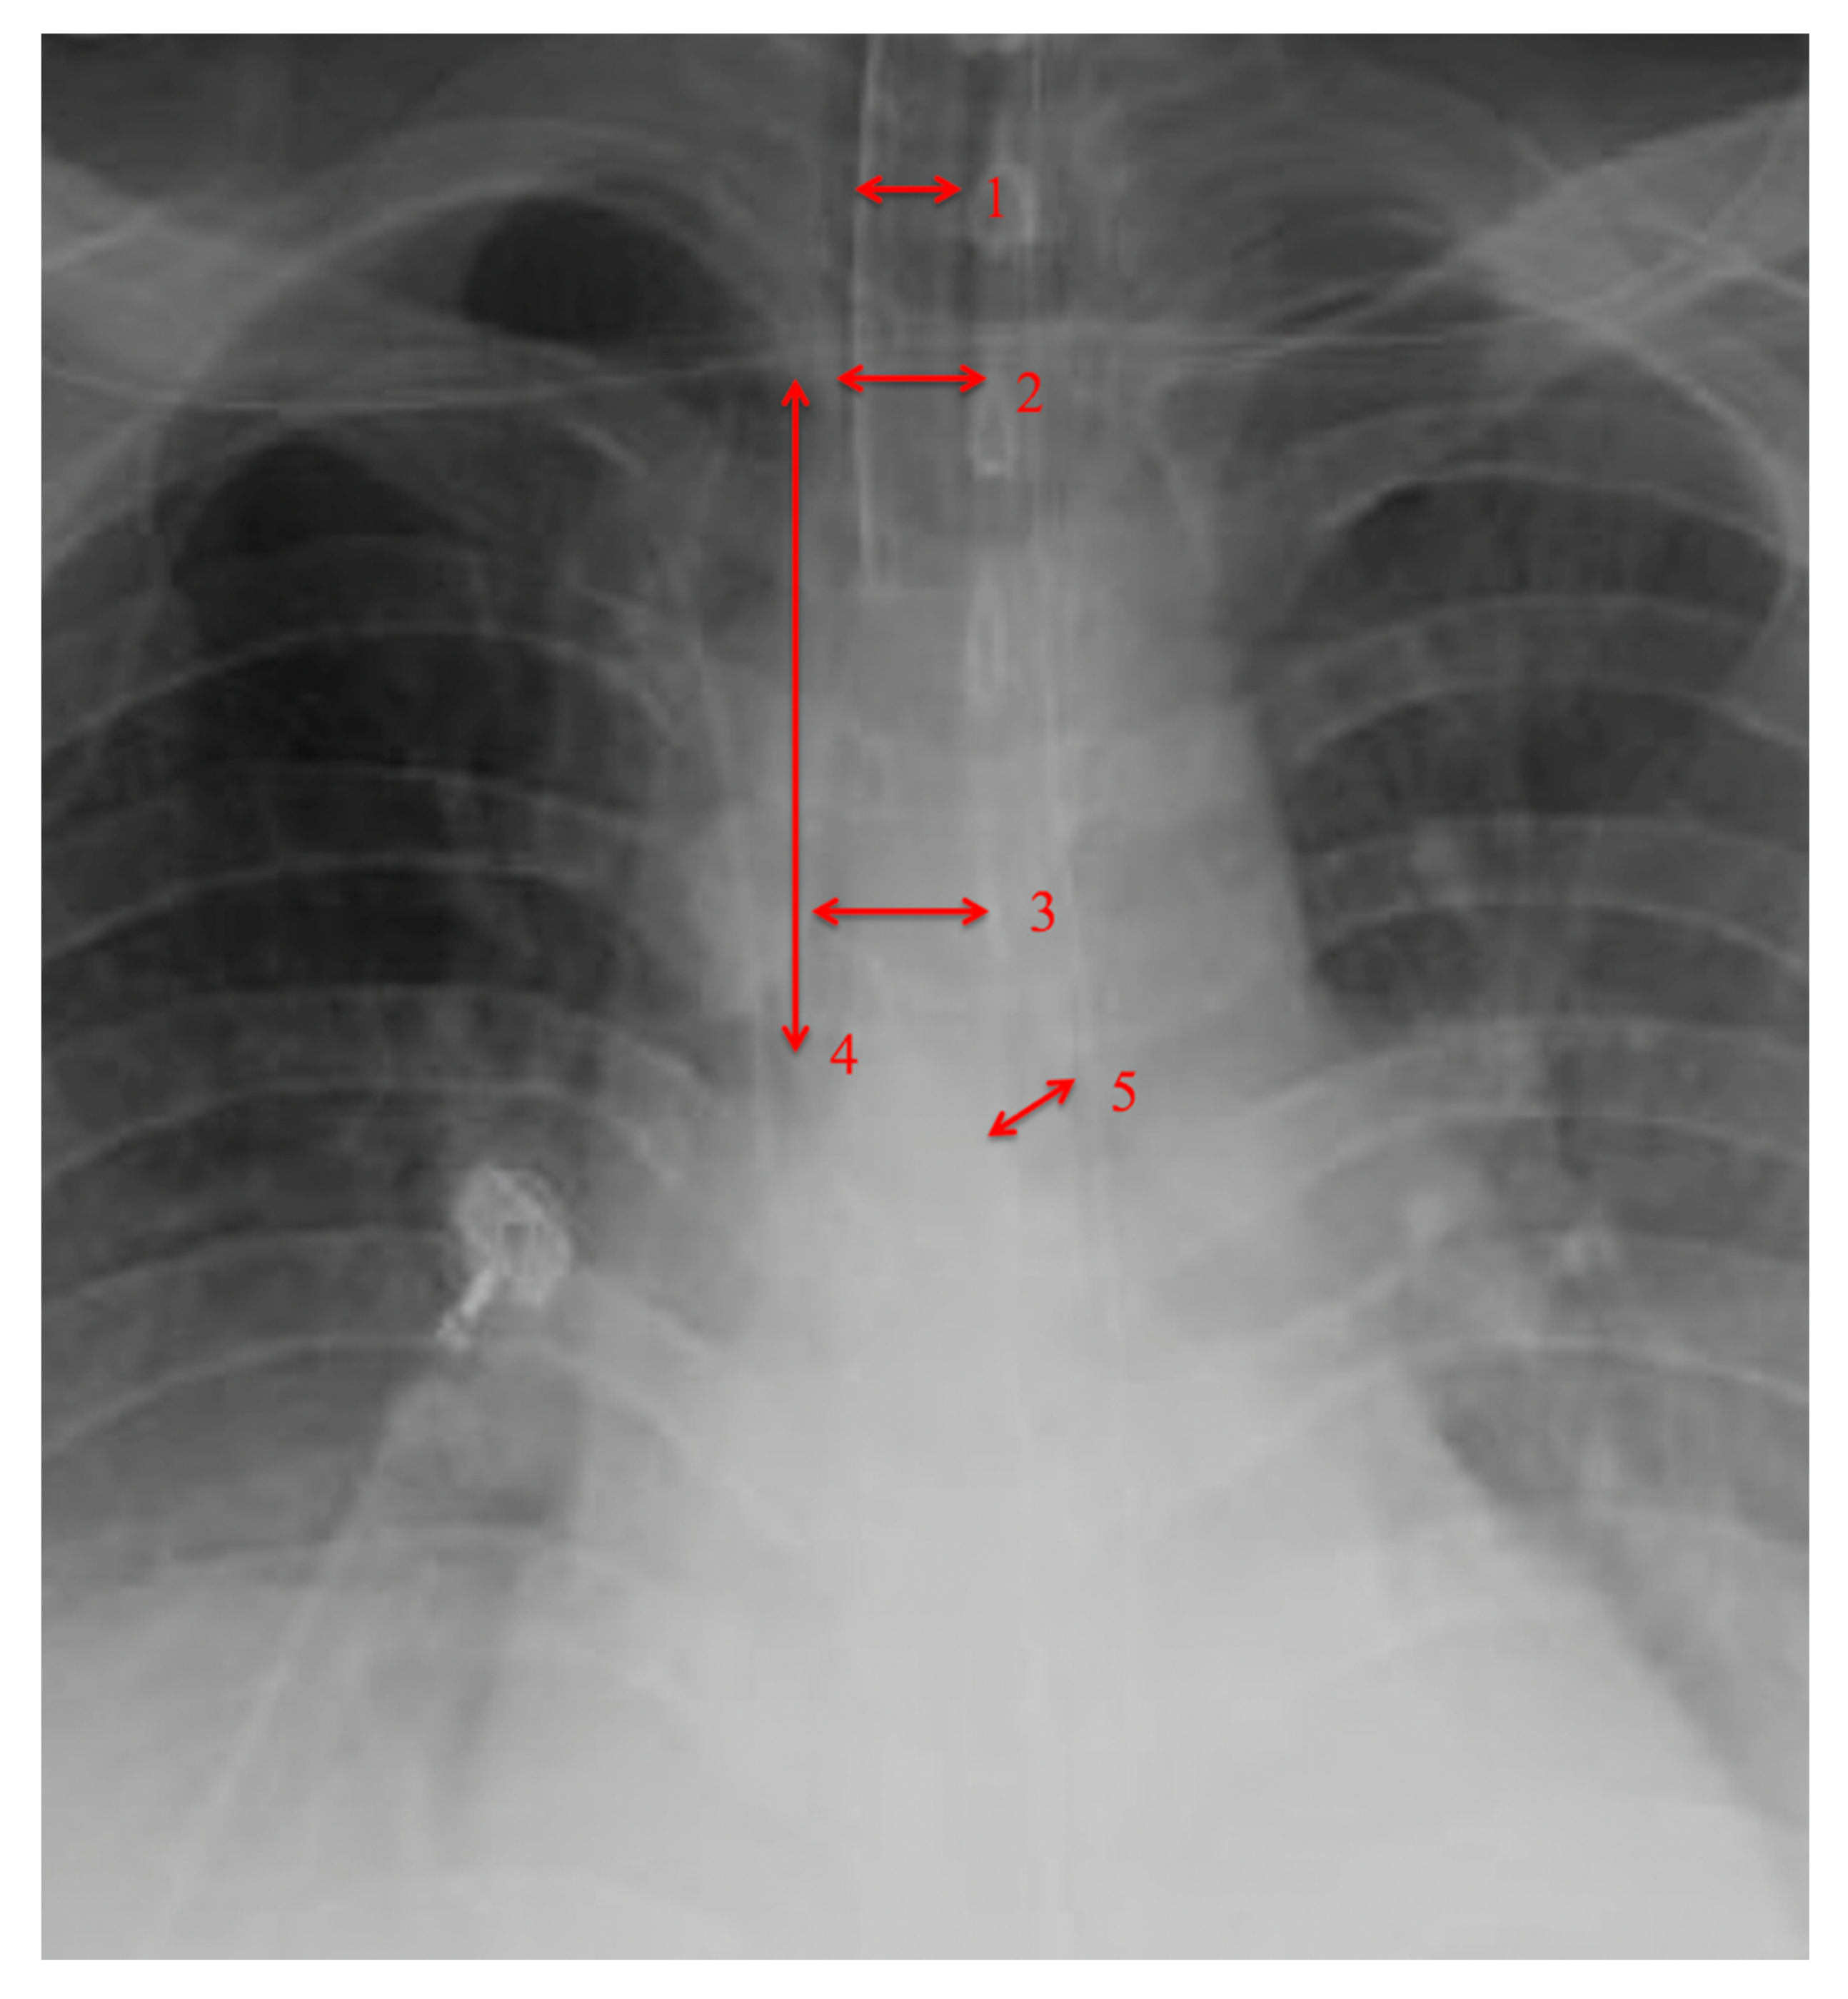

| Tracheal Diameter | 15.75 (±4.03) |

| Intrathoracic Tracheal Length | 82.09 (±20.82) |

| Left main bronchus | 12.765 (±2.85) |

| • Tracheal Diameter Measured at 1st Rib > 15 mm |

| • Tracheal diameter measured at carina > 15 mm |

| • Intrathoracic Tracheal length from 1st rib to carina > 80 mm |

| • Left main-stem bronchus diameter > 10 mm |